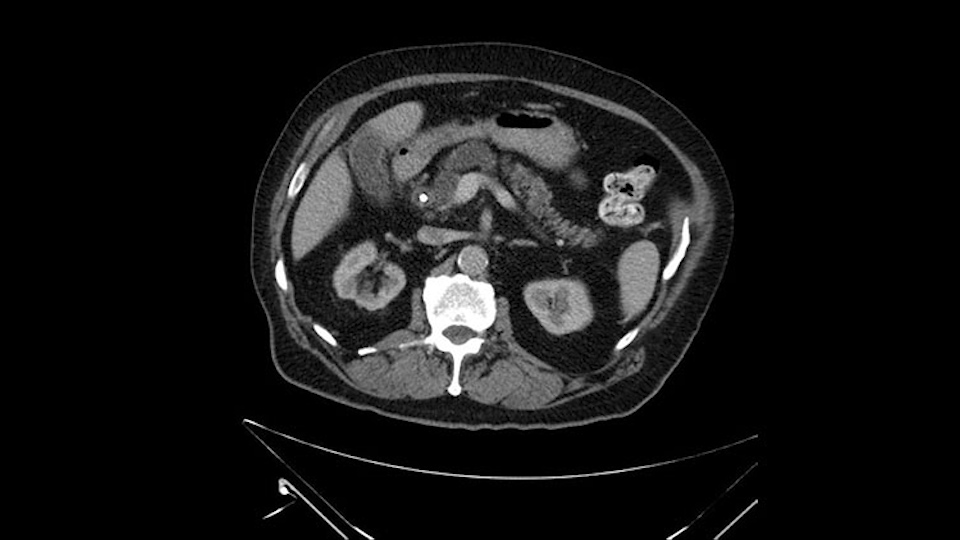

Then either through the coronal or the axial, I’ll do both. Look at the SMA -which is here- I had already looked at it and I don’t see any involvement. There’s the SMA with a nice fat plane between the SMA and the tumor. Over here you can see on the axial, there’s the SMA. Everything on the right side of the SMA has got some nice black around it, which is fat, which means probably no tumor [no tumor, no tumor]. Follow it up to the origin, coming off the aorta. So those are the two technical things that I worry about: the SMA and the SMV.

The initial hepatic flexure mobilization and the Kocher procedure is then going to enable me to understand the uncinate process of this patient, which should not be a problem, again. But the initial pictures had shown a degree of touching. I would not even say involvement or abutment; a degree of touching with the superior mesenteric vein. So that would give me an early chance to assess how the superior mesenteric vein is in this patient. So this would be the initial slowing down moment.

Other important points are: the dissection of the uncinate process which must be done very carefully, the ligation of the venous branches there, and looking for the inferior pancreaticoduodenal arteries coming from the superior mesenteric artery during the dissection of the uncinate process.

The first steps of a pancreaticoduodenectomy involve ensuring the CT findings are correct: exploring for signs of metastatic disease, peritoneal implants involving the omentum or the undersurface of the diaphragm and if again this is confirmed exploration that there's no metastatic disease, I begin the mobilization and really determining the relationship of the tumor with the major visceral vessels. I start by an extended Kocher maneuver, identify the superior mesenteric vein below the neck of the pancreas. They’re very thin walled vessels and as you're dissecting you have to use the ultimate care and meticulously dissect the superior mesenteric vein, ligate the anterior branches and begin the dissection from below to under the neck of the pancreas. At this point, if there's no reason to be concerned about whether there is any vascular invasion below, I usually take the gallbladder down. I mobilize the common hepatic duct above the insertion of the gallbladder. This patients already has a stent in place. So I would divide the bile duct at this point. This facilitates the dissection of the anterior surface of the portal vein and as I would expect looking at this imaging that there is nothing to be concerned about in terms of vascular involvement.

Once the pancreatic neck is divided, you sort of roll or flip the neck of the gland over, exposing the anterior surface and the right lateral surface of the portal vein-SMV complex. Continue that dissection down. Oftentimes you can really continue your dissection right along the uncinate on the SMA. Again a little advantage of this patient having an ampullary lesion, there's likely to be no evidence of extension into the uncinate so you don't have to worry quite as much about the margin at the uncinate as you would with a pancreatic head cancer. Keeping in mind that you will have an inferior pancreatic duodenal artery in there that you want to try to identify and ligate individually. At some point along that time I go to the ligament of Treitz. Clean an area of the ligament of Treitz of its mesentery, divide it there with a linear stapler. I use the Harmonic scalpel to mobilize the proximal 10-inches or so of small intestine down to the ligament of Treitz completely mobilize the ligament of Treitz past the jejunal limb underneath the root of the mesentery and then carefully dissect the third and fourth portion of the duodenum’s mesentery as well as the remaining uncinate to complete my resection. I will have marked and sent frozen section from the pancreatic neck at the time that I do the resection of that part of the gland so that I have that information back by now. I would also probably get a margin on the uncinate and a margin on the bile duct just for completeness, although for an ampullary carcinoma that would be unlikely to have a positive extension.